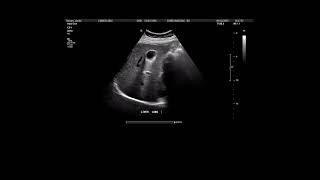

SIDUO 2024 - Why do we need ophthalmic ultrasound?